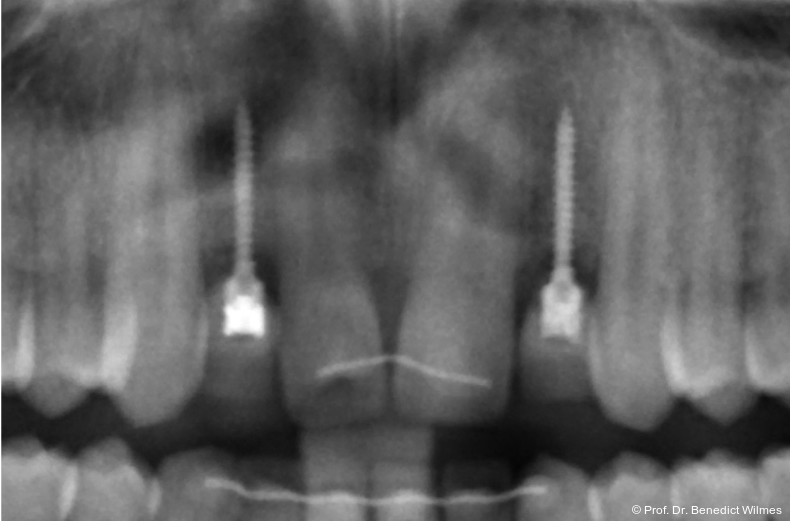

Ein 14-jähriger Patient wurde bei Aplasie der beiden oberen seitlichen Schneidezähne mit dem Ziel der beidseitigen Lückenöffnung kieferorthopädisch therapiert (Abb. 1a+b). Zum Ende der kieferorthopädischen Behandlung wurden zwei Miniimplantate in Regio 2er als temporärer Zahnersatz inseriert (Benefit System, PSM, 2 x 13 mm, Abb. 2a+b). Nach Abdrucknahme wurden Kronen auf den Peek-Abutments modelliert und diese mit Kunststoff auf die Abutments geklebt (Abb. 3a–d). In den Abbildungen 3 und 4 sind die klinischen und röntgenologischen Nachkontrollen innerhalb der nächsten achteinhalb Jahre dokumentiert. Man erkennt einen sowohl in der Höhe als auch in bukkopalatinalen Breite verbleibenden gesunden Knochen ohne Anzeichen einer Atrophie. Im Alter von 23 Jahren wurden die definitiven Implantate ohne die Notwendigkeit einer Augmentation eingesetzt (Abb. 5) und nach Einheilung prothetisch versorgt (Abb. 6a–e und Abb. 7a–c).